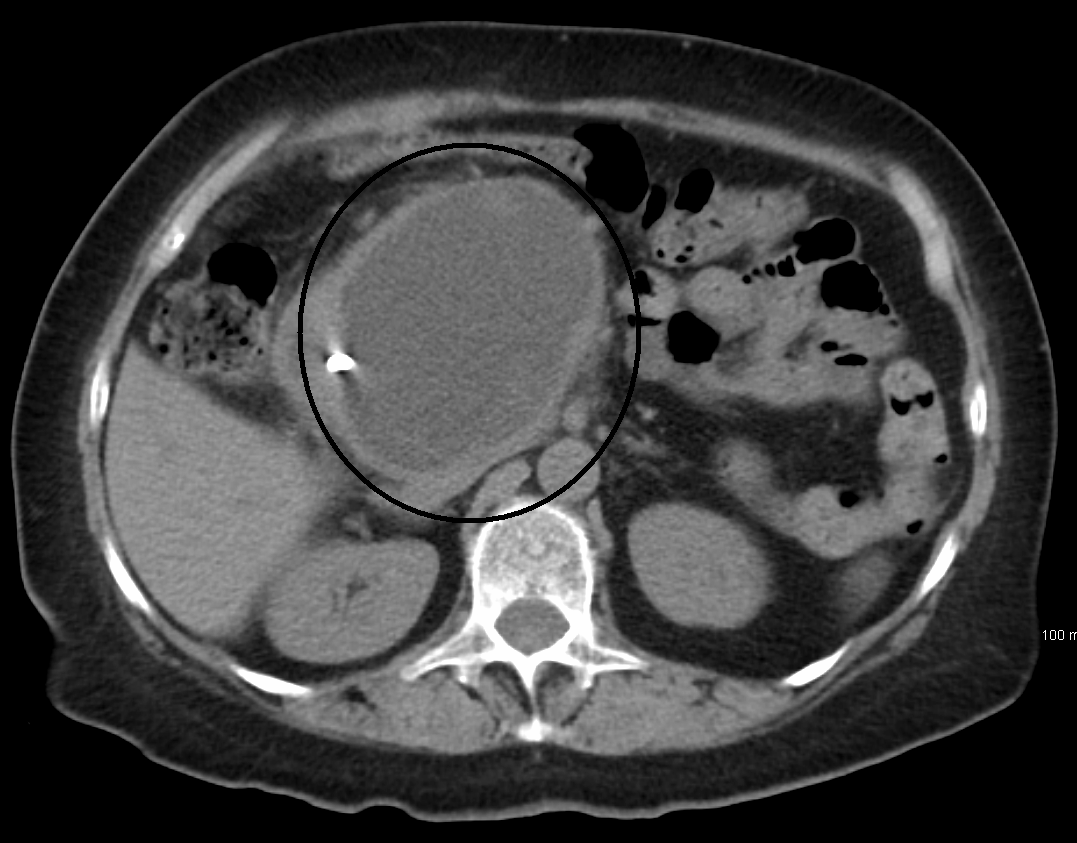

54 yo pt with acute pancreatitis admission several weeks ago shows the following CT imaging. What is the diagnosis? Explain what it is

Pseudocyst

Walled off collection of oedema with no surrounding epithelium

Usually occurs for weeks after acute pancreatitis

♦ Most resolve wo intervention. Feared outcome is rupture causing peritonitis. Can also become infected causing an abscess